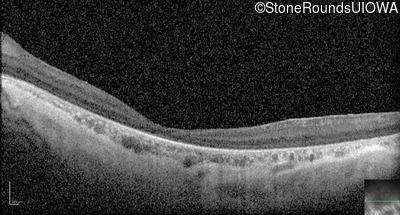

Optical Coherence Tomography - Left - 10/350 sc

Exemplar / OCT Stack